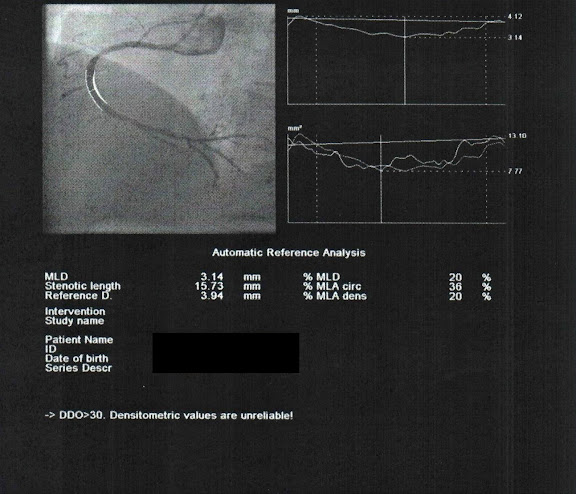

第三個堵塞位置在一個分岔點之前。

電腦分析堵塞面積也是有95%。

從另一個角度來看,在右上角那個分叉點幾乎都要斷開了。

一樣先用3.0mm的氣球先把堵塞的地方撐開。

結果一撐開卻是把堵塞的硬塊推到另一邊去了,將另一邊原本沒塞住的血管塞起來了。

伸到另一邊去再把它推回來一些些。

讓兩邊平均一點。

等待5min過後,看起來有撐開沒再縮回去。

處理結果由原本的95%變成27%,效果還算不錯。